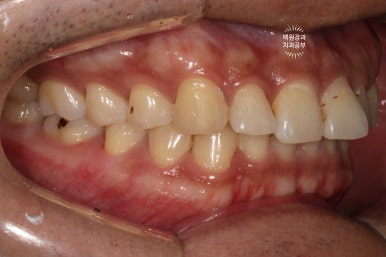

고개를 돌려 좌측을 보시면, 우측에서 보이던 것과 달리 치아 표면이 깨져서 구멍이 나신 것을 보실 수 있죠?

좌측 측면 사진에서 치료 결과가 더 극명하게 드러나는 것 같습니다.

사실 이 정도로 충치가 진행되시면, 기본적으로 국소마취가 필수입니다.

국소마취에 대한 영향으로 잘~ 보시면 잇몸이 조금 더 하얀 상태인 것을 보실 수 있죠? 치과용 리도카인 국소마취제는 약간의 에피네프린이 첨가되어 있어, 혈관수축을 유도하고 치료 시 출혈이 최소한이 되게끔 도와줍니다.

마치 숨은그림찾기 같지만.. ㅎㅎ 옆면 충치를 레진치료로 마무리 함으로써, 뒤에서 보아도 깔끔해진 모습을 볼 수 있습니다!!